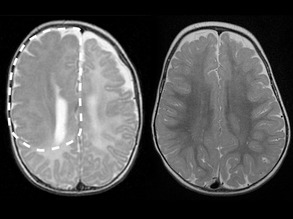

Essential Brains

03